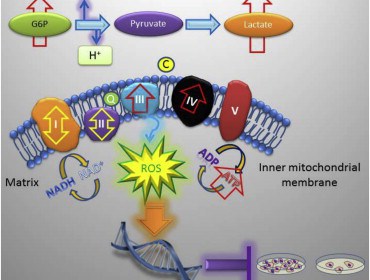

In healthy cells, TRAP-1 is an important regulator of metabolism and has been shown to regulate energy production in mitochondria, organelles that generate chemically useful energy for the cell. In the mitochondria of cancer cells, TRAP-1 is universally overproduced. The study, which appears in the journal Cell Reports, shows how ‘knockout’ mice bred to lack the TRAP-1 protein compensate for this loss by switching to alternative cellular mechanisms for making energy.

The researchers found that in their knockout mice, the loss of TRAP-1 causes mitochondrial proteins to misfold, which then triggers a compensatory response that causes cells to consume more oxygen and metabolize more sugar. This causes mitochondria in knockout mice to produce deregulated levels of ATP, the chemical used as an energy source to power all the everyday molecular reactions that allow a cell to function.

This increased mitochondrial activity actually creates a moderate boost in oxidative stress (‘free radical damage’) and the associated DNA damage. While DNA damage may seem counterproductive to longevity and good health, the low level of DNA damage actually reduces cell proliferation, slowing growth down to allow the cell’s natural repair mechanisms to take effect.

TRAP-1 knockout mice have reduced age-associated pathologies. Loss of TRAP-1 upregulates oxidative phosphorylation and glycolysis transcriptomes. TRAP-1-deleted cells have deregulated mitochondrial respiration and enhanced glycolysis. TRAP-1 deletion induces oxidative stress, DNA damage, and reduced cell proliferation. Deletion of the Mitochondrial Chaperone TRAP-1 Uncovers Global Reprogramming of Metabolic Networks. Altieri et al 2014.